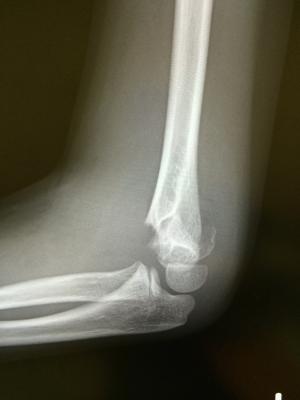

ひじの骨折

最近の遊び?ローラーボードでバランスを崩し転倒されました。

近くの整形外科よりレントゲンの情報提供をうけ、リハビリを

する予定です。

医師からの同意があれば、接骨院でも骨折のリハビリができますよ。